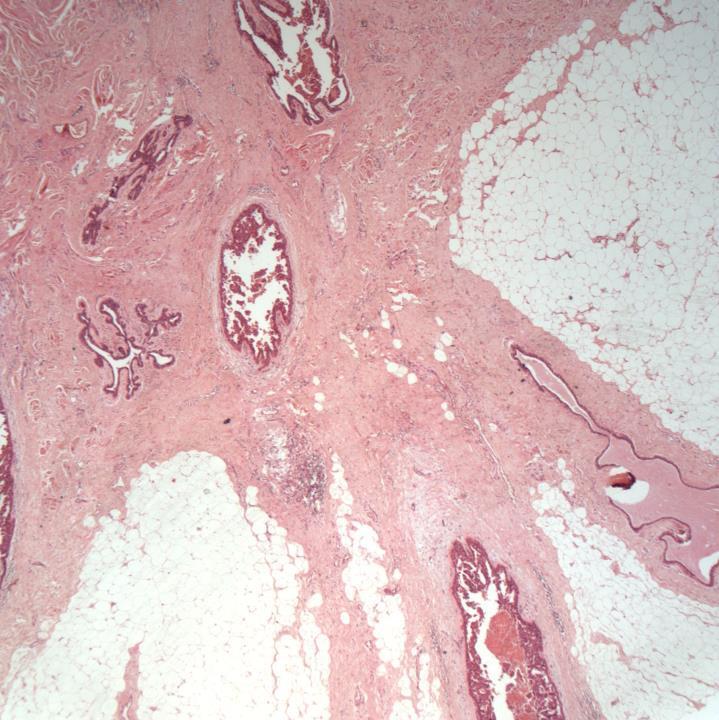

Case 11

◼ Radial scar.

◼ No atypia or malignancy.

◼ Radial scar/complex sclerosing lesion:

Architecture

Fibroelastotic stroma preserved myoepithelium

No epithelial atypia

DD

Tubular Carcinoma/grade 1 carcinoma

◼ Absent myoepithelium

◼ Desmoplastic stroma

◼ Epithelial atypia

Radial scar

◼ On core biopsy: B3

◼ Comment on presence/absence of atypia

◼ Second line VAB (VAE)